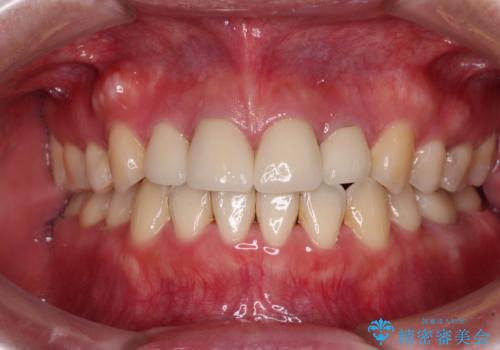

出っ歯による口の閉じにくさを治したい ワイヤー装置を用いた抜歯矯正

担当医 藤巻太一朗